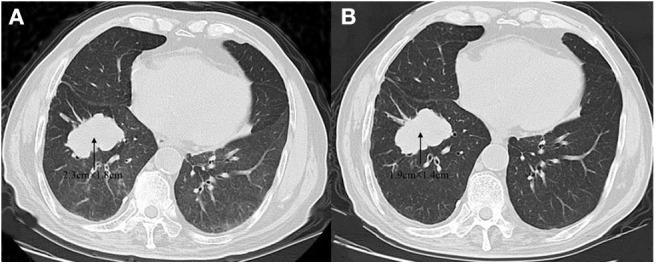

Oncogenic mutations in the epidermal growth factor receptor () occur frequently in patients with lung cancer. These mutations may serve as critical predictive biomarkers in patients with non-small cell lung cancer (NSCLC). Among them, exon 18-25 kinase domain duplication (-KDD) mutations have been identified as a novel gene subtype in NSCLC. We reported a rare case of a 59-year-old male diagnosed with adenocarcinoma. A biopsy revealed an -KDD identified by the next generation sequencing (NGS). Effective treatment outcome has been observed after administration with afatinib. This case highlights that comprehensive NGS technique is valuable in detecting novel genetic mutations in tumors.

表皮生长因子受体()的致癌突变在肺癌患者中频繁发生。这些突变可能是非小细胞肺癌(NSCLC)患者的关键预测生物标志物。其中,外显子18 - 25激酶结构域重复(-KDD)突变已被确定为NSCLC中的一种新型基因亚型。我们报告了一例罕见病例,一名59岁男性被诊断为腺癌。活检显示通过下一代测序(NGS)鉴定出-KDD。给予阿法替尼后观察到了有效的治疗效果。该病例突出了全面的NGS技术在检测肿瘤新基因突变方面的价值。